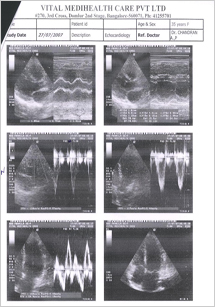

Echocardiography was done and shows that the valves are much better, the abnormal murmur heard using stethoscope have almost disappeared. Echocardiography report is shown in FIG3. Placebo continued

FIG 3:- Echocardiography report of 27th Nov. 2007

Echocardiography was done indicating a normal heart and patient is un symptomatic. Final Echocardiography was done and shown in FIG 4

FIG 4:- Echocardiography report of 4th JAN 2008